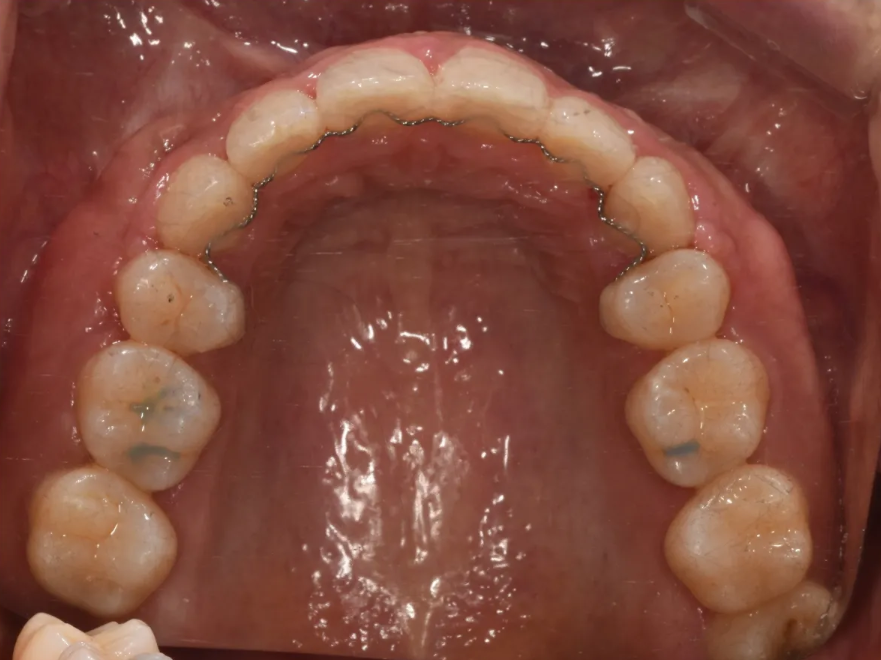

윗니와 아랫니 각각 역시 매우 예쁘게 배열된 모습을 확인하실 수 있습니다.

치료 후 윗니 배열 – 깔끔하게 정리된 모습